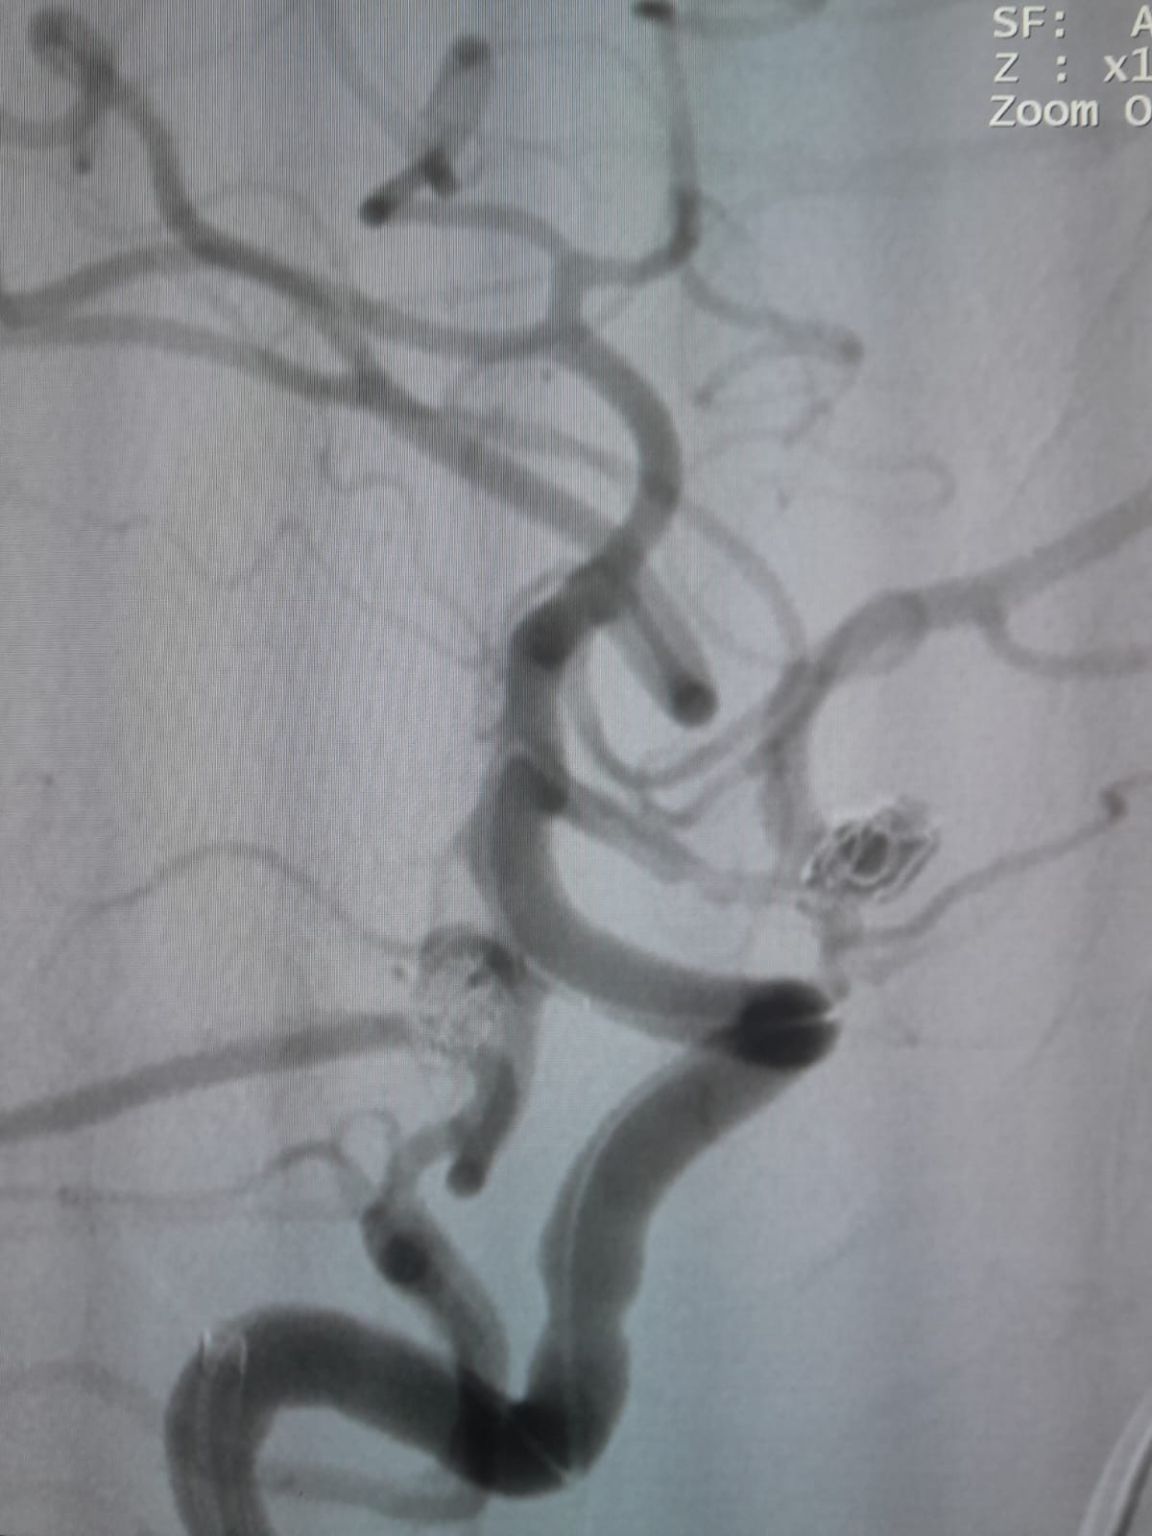

У пациента была диагностирована недавно обнаруженная мешочковая аневризма передней сообщающейся артерии (AComA) и аневризма задней сообщающейся артерии (PComA), которые ранее лечились с помощью спиральной эмболизации. Последующая визуализация выявила остаточное заполнение аневризмы PComA, требующее дополнительного вмешательства.

Во время наблюдения было отмечено остаточное наполнение в ранее обработанной аневризме задней сообщающейся артерии. Команда повторно зашел на сайт с помощью Frepass®Одноразовый микрокатетер (TJMC18 Plus) и успешно развернутый Nuva®Отвод потока (TJED-D-4.5-16), который продемонстрировал идеальное расположение стены и отличное отклонение потока, что привело к весьма удовлетворительным результатам лечения.